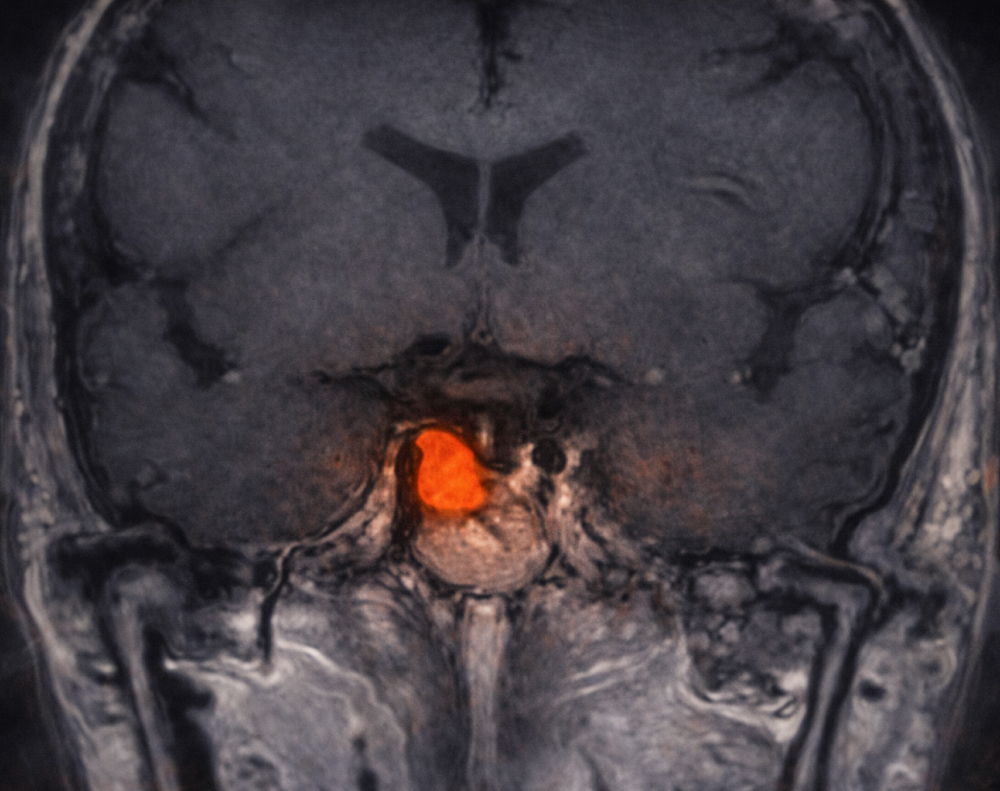

- Resonancia magnética para localizar tumores en la hipófisis (en el caso de enfermedad de Cushing).